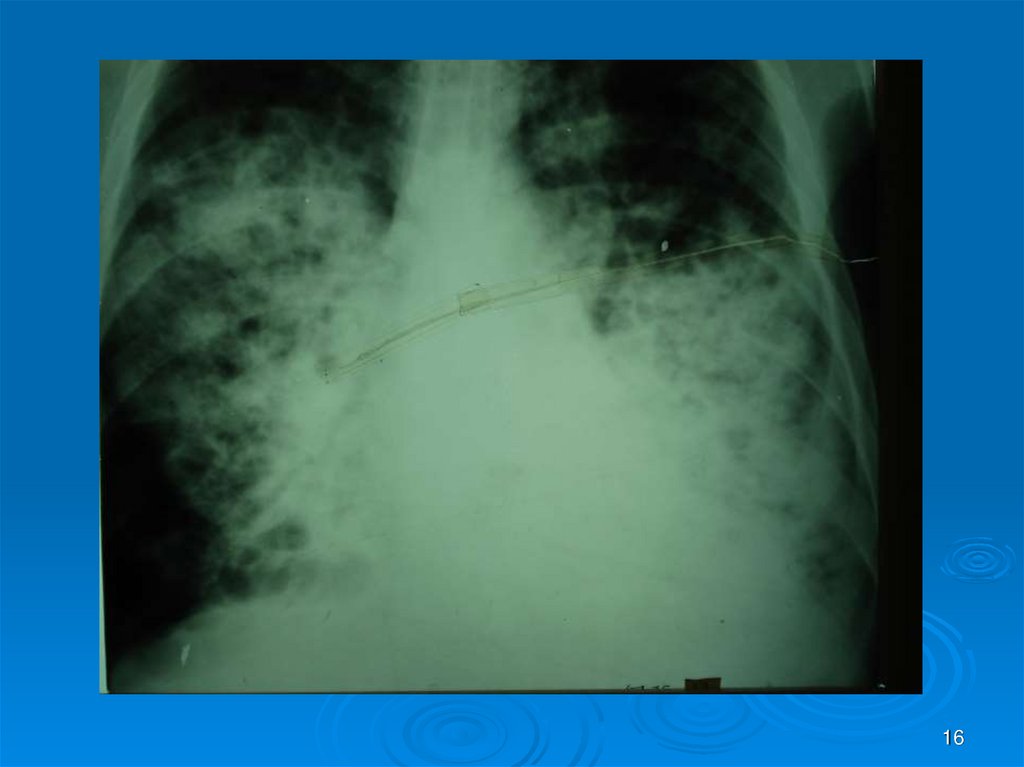

Каждый из вас должен интерпретировать Rснимки (всего 30) в ММ-презентации: назвать

заболевание, его локализацию, если осложнение

заболеваний – то указать какое. На снимках могут

быть пневмония (очаговая, сегментарная,

долевая), абсцесс легких I и II стадии, гангрена

легких, плеврит, ХОБЛ и сходные с ними болезни

легких, требующие дифференциальной

диагностики (туберкулез и др.). Успехов в работе!

16.

16